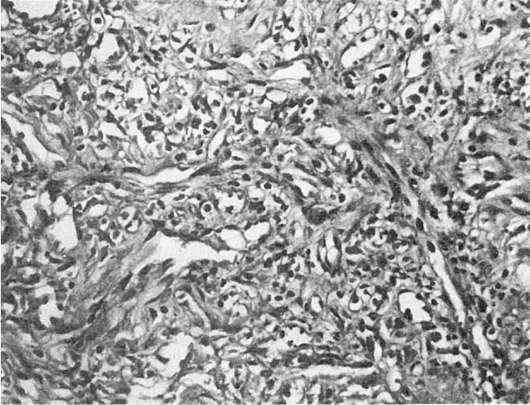

Рис.

254. Саркома Капоши у больного СПИДом. Поражение кожи

хаотично расположенных тонкостенных сосудов с хорошо определяемым эндотелием и пучков веретенообразных клеток (рис. 254). В рыхлой строме часто видны кровоизлияния и скопления гемосидерина. У больных СПИДом саркома Капоши имеет злокачественный характер и отличается от классического варианта генерализацией процесса с поражением лимфатических узлов, желудочно-кишечного тракта, легких и других внутренних органов.